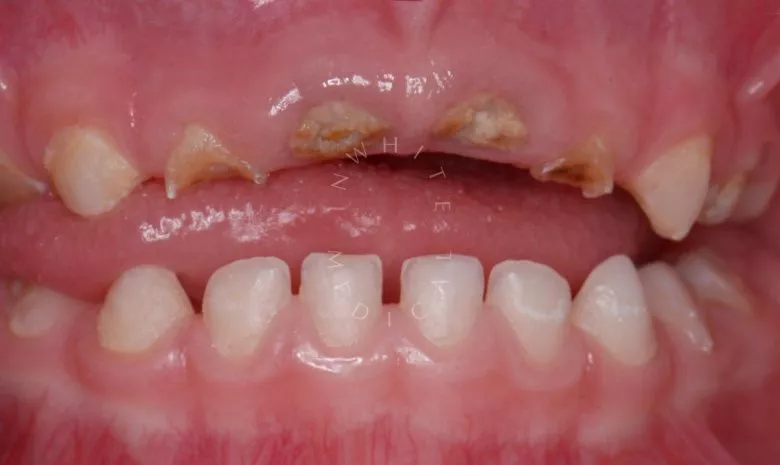

Лечение под наркозом - установка коронок и профессиональная гигиена у детей

етская стоматология лечение под наркозом. Лечение под наркозом - установка коронок и профессиональная гигиена у детей - до процедуры

етская стоматология лечение под наркозом. Лечение под наркозом - установка коронок и профессиональная гигиена у детей - после процедуры